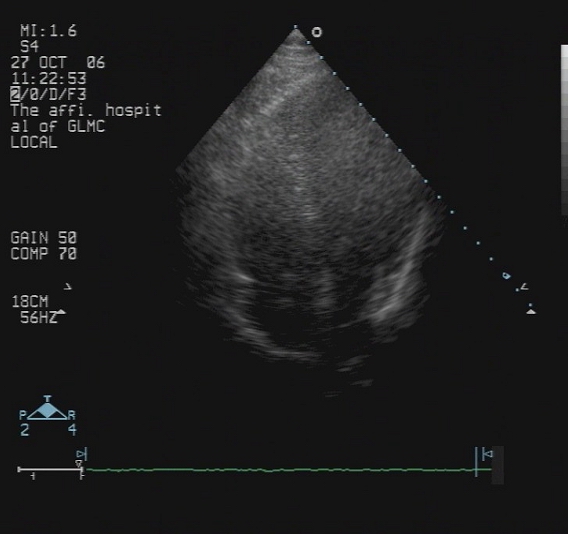

心脏彩超:

● RVOT:33mm,AOV:30mm,LAS:72mm,RAS:65mm,LAD:61mm,LVPWD:10mm,IVS:10mm,RVD:22mm,EF:0.67,FS:30%。全心增大,主动脉瓣反射增强,余瓣膜柔软不厚,闭合良好,室间隔与左室后壁不厚,呈逆向运动。房室间隔连续性完整。

提示:全心大